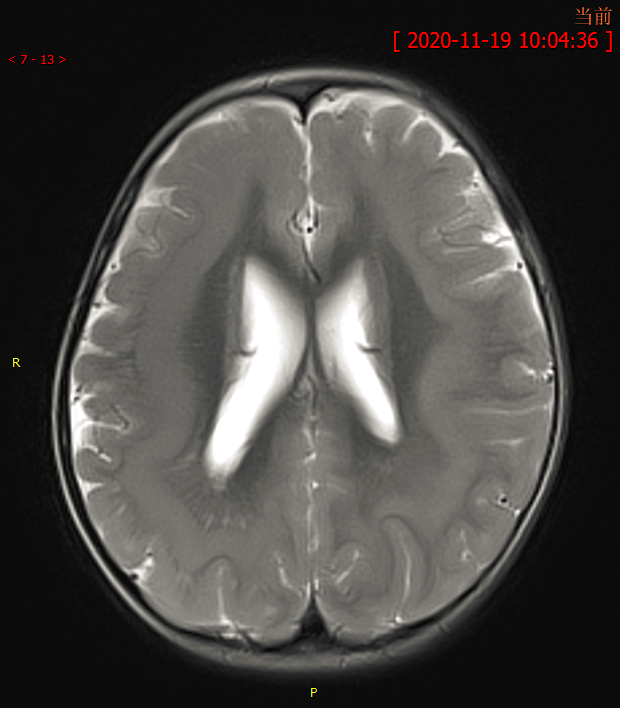

磁共振和弥散张量成像(dti)数据,同时探究他们脑灰质和白质形态学特征